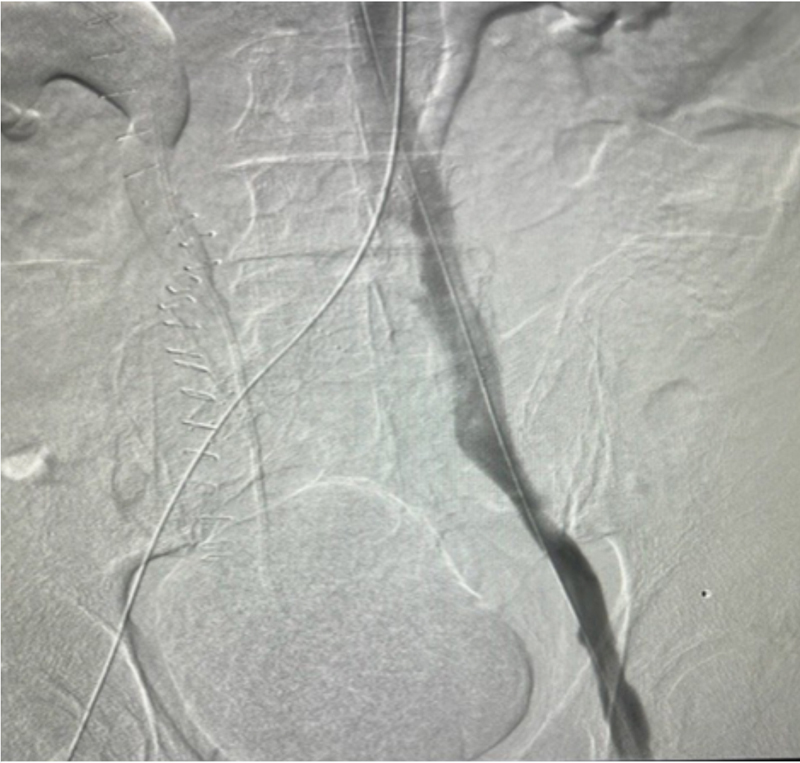

During the mechanical thrombectomy, the patient was placed in the prone position. Bilateral popliteal veins were accessed under ultrasound. Venogram confirmed extensive thrombus in the right and left iliac veins, as well as in the IVC (Figures 1 and 2). Due to IVC involvement, extra-large discs were deployed from the left popliteal vein and above the IVC thrombus for embolic protection. A 13Fr clot retrieving device was inserted on the right. Six passes were made with the clot retriever basket, removing all available IVC and right sided thromboses, which were sub-acute and chronic (Figure 3). The 13Fr clot retriever sheath was then moved to the left popliteal, where five passes were made removing the left-sided thrombi, which also were found to be extremely compacted and likely chronic (Figure 4). The complete thromboses removed are pictured in Figure 5. The patient then received bilateral stents and flow was restored. The patient was discharged two days later on anticoagulation with significant improvement of the lower extremity and pelvic edema.

Figure 2

Figure 2. Right external iliac vein and IVC pre-thrombectomy venogram.